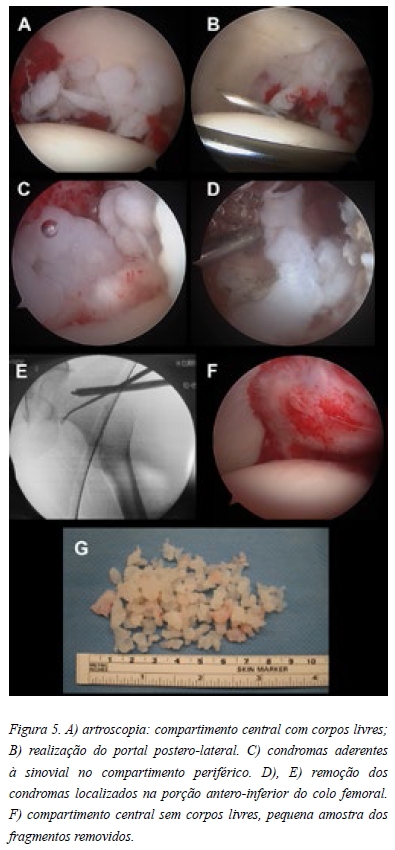

A hipótese diagnóstica colocada foi de condromatose sinovial primária. Desta forma a paciente foi proposta para artroscopia da anca com carácter diagnóstico e terapêutico. Iniciámos o procedimento pelo compartimento central utilizando o portal antero-lateral (visualização e trabalho) e médio-anterior (visualiazação e trabalho) sendo possível observar vários condromas no fundo acetabular (Figura 5A). Posteriormente realizou-se o portal póstero-lateral com intuito de assegurar a remoção de todos os corpos livres da porção posterior do compartimento central (Figura 5B). No compartimento periférico procedeu-se à libertação e remoção dos condromas aderentes à sinovial (Figura 5C). Para melhorar o acesso à porção antero-inferior do colo femoral tivemos necessidade de realizar o portal anterior, com intuito de remover o maior número possível de condromas (Figura 5 D, E). O objectivo final foi a remoção de todos os condromas identificáveis (Figura 5 F, G). Constatou-se um labrum degenerado, mas estável (Figura 6 A) e uma cartilagem acetabular com lesões grau II de Outerbridge (Figura 6 B). De seguida procedeu-se a osteoplastia femoral (Figura 6 C). O exame histológico confirmou o diagnóstico.